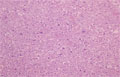

• (11)Undifferentiated (anaplastic) carcinoma of the thyroid

Macroscopic findings. Autopsy case. The thyroid tumor rapidly proliferating and invading into the skin around the neck. This is a typical example of a highly malignant tumor